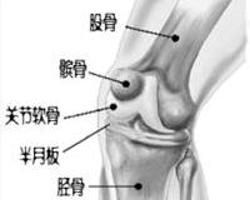

5.膝關節正、側位X照片,顯示髕骨、股骨髁、脛骨平台關節緣呈唇樣骨質增生,脛骨髁間隆突變尖,關節間隙變窄,軟骨下骨質緻密,有時可見關節內游離體。